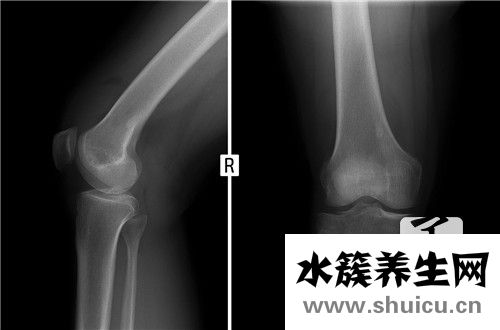

骨刺是骨骼增生的結果,在X光上面看上去,好像從骨骼周圍長出去一根尖長的東西,因此被稱作「骨刺」。

如果是有肥胖癥問題或者經常需要久站的工作中很有可能會給骨節非常大的壓力,而此壓力會造成 骨節里的軟骨損壞,使骨節越來越不穩定,骨節以便提升我們的穩定性,會增生骨刺以提升穩定性。因此,非常容易增生骨刺的地區多坐落于負重的骨節及其活動力較高的骨骼,如同膝蓋關節及其腰椎骨。